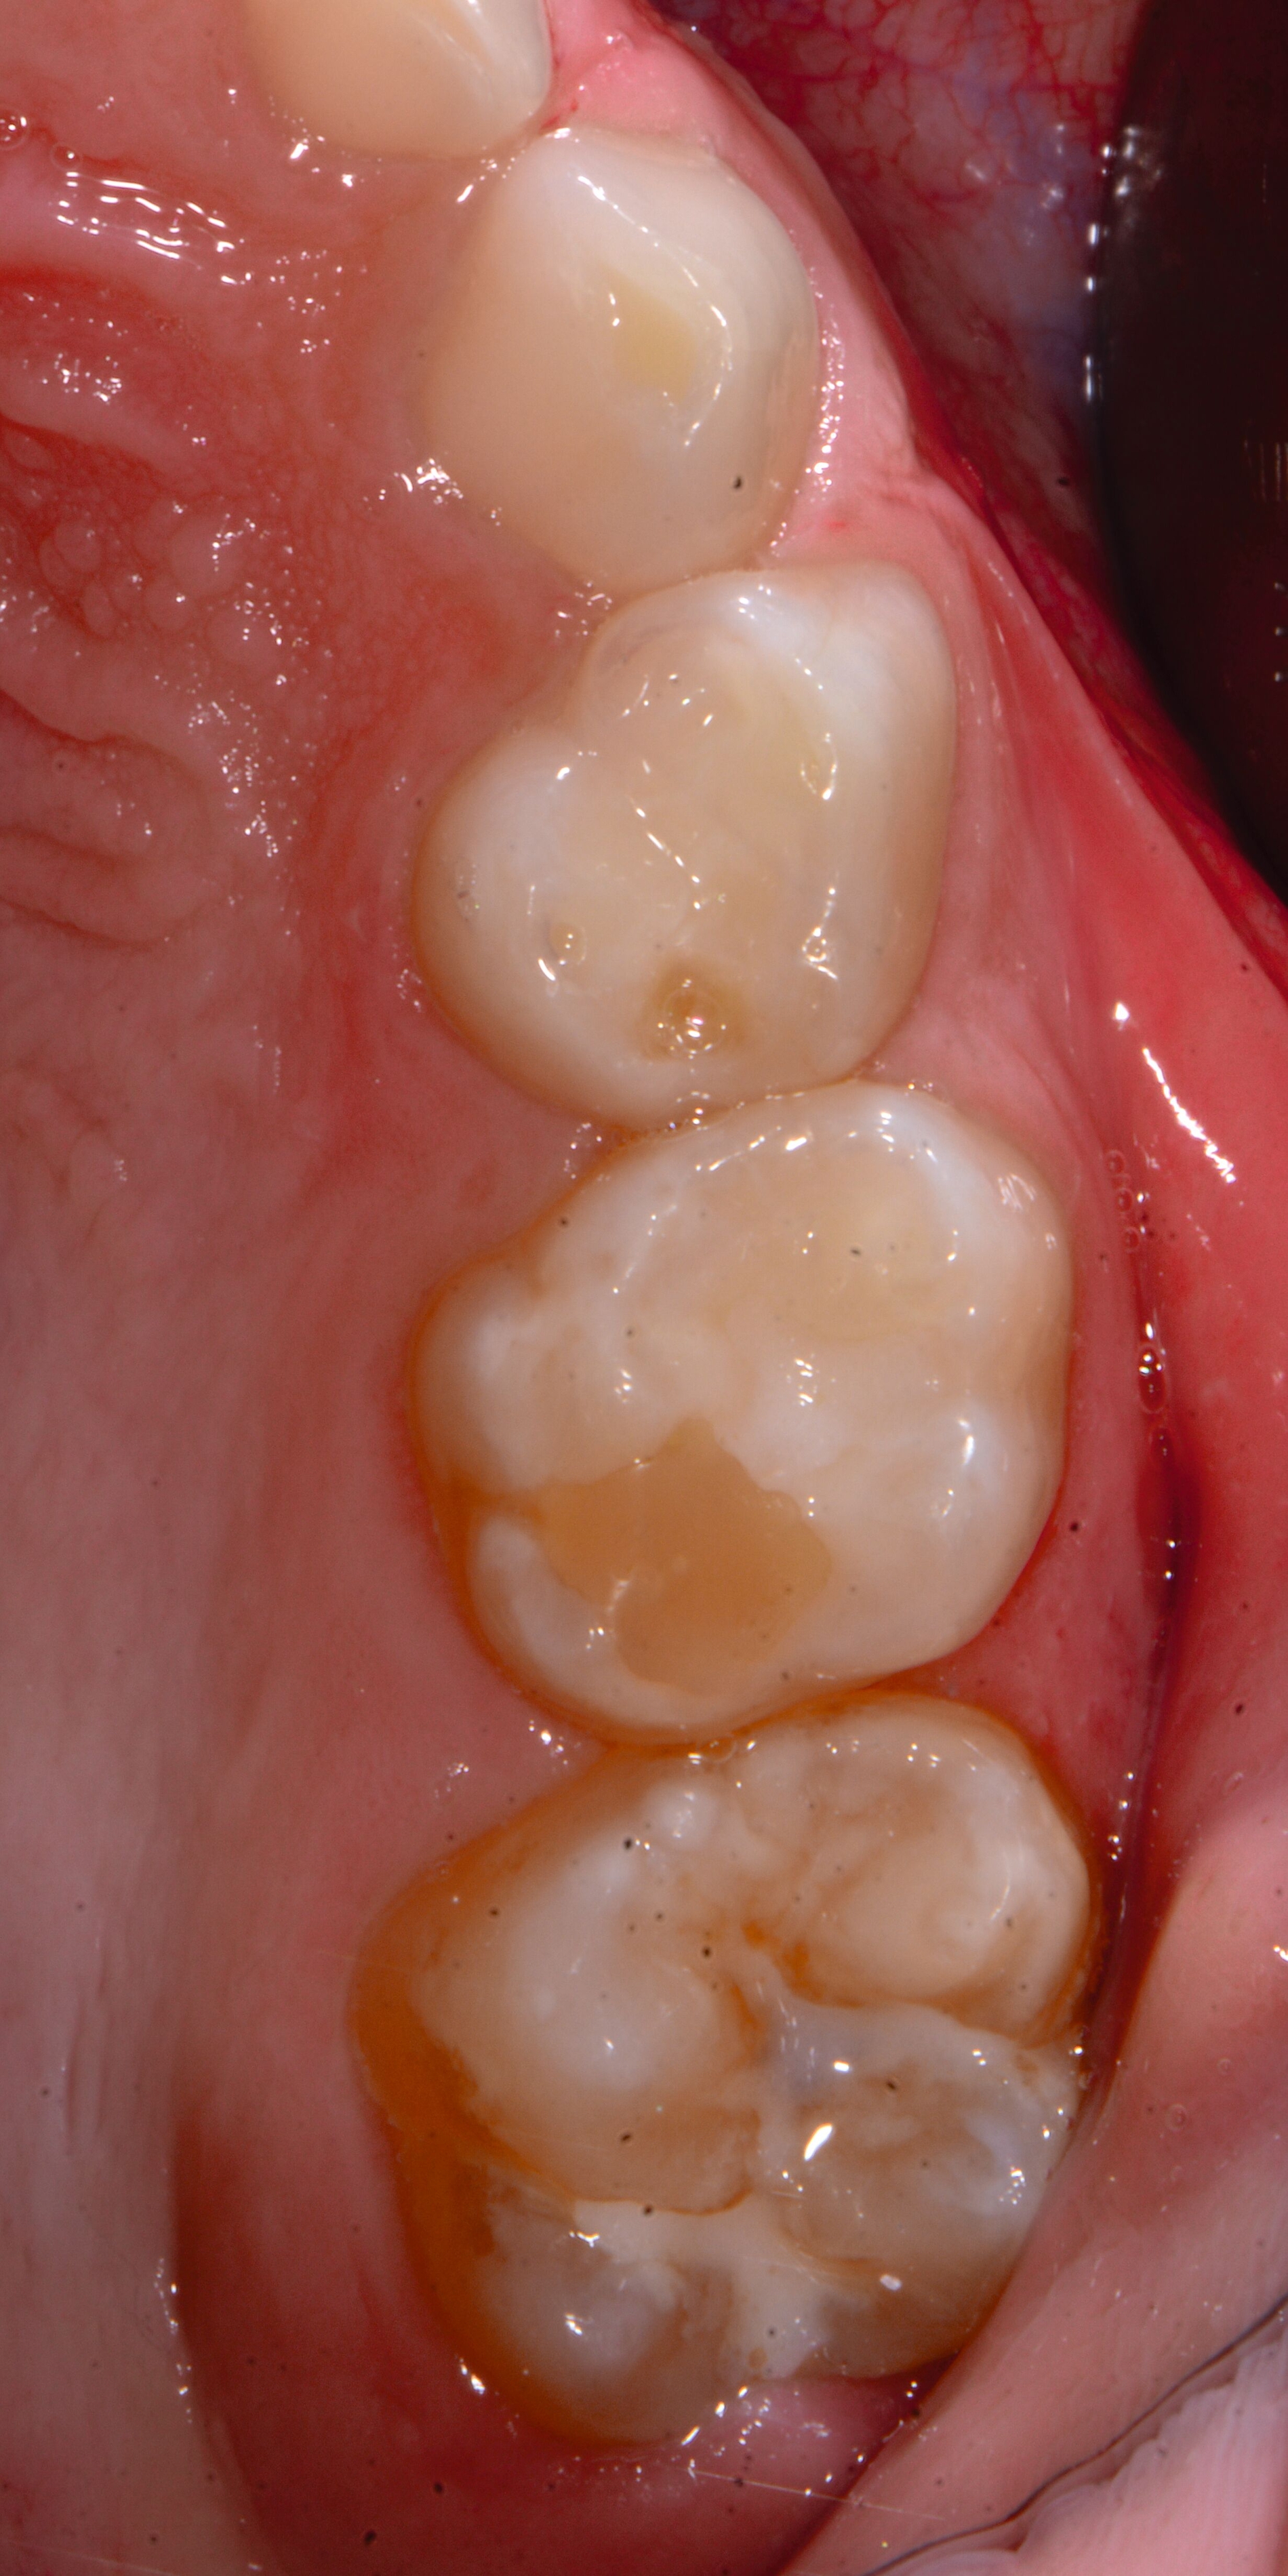

Das klinische Erscheinungsbild an bleibenden Zähnen zeigt typischerweise weißlich-gelbe bis gelblich-braune Opazitäten, die zumindest in einigen Bereichen durch eine scharfe Abgrenzung (engl.:„demarcated opacities“) zum gesunden Zahnschmelz charakterisiert sind (Abbildungen 3 und 4). Die abgegrenzten Hypomineralisationen befinden sich mehrheitlich im Bereich der inzisalen Kronenhälfte unabhängig von dem Auftreten an Front- oder Seitenzähnen. Die Ausprägung am Zahn kann dabei auf einzelne Areale oder Höcker begrenzt sein.

Bei einer schwerwiegenderen Ausprägung sind Zahnflächen vollständig betroffen, mitunter alle Zahnflächen an einem Zahn. Die Verteilung in der Dentition beziehungsweise an den Indexzähnen ist gleichermaßen variabel und betrifft nicht nur die Defektgröße, sondern auch die Farbe und Festigkeit. Was die Festigkeit betrifft, gilt als die Faustregel: Je dunkler die Farbe des Schmelzes, umso weicher beziehungsweise poröser und damit minderwertiger wird dessen Qualität sein. Damit reduziert sich seine kaufunktionelle Belastungsfähigkeit, was insbesondere an ersten bleibenden Molaren von klinischer Relevanz ist.

Für die Dokumentation und Klassifikation der MIH wurden verschiedene Systeme vorgeschlagen. Als historisch und veraltet gilt der (modifizierte) DDE-Index. Demgegenüber haben die Kriterien der EAPD – abgegrenzte Opazitäten (Abbildung 3 und 4), Schmelzeinbrüche (Abbildung 5), atypische Restaurationen (Abbildung 6) – mittlerweile die weiteste Verbreitung gefunden. Diese wurden 2003 erstmals zur Beschreibung der MIH auf empirischer Basis publiziert [Weerheijm et al., 2003] und den Jahren 2010 und 2022 im Rahmen der damaligen MIH-Workshops bestätigt [Lygidakis et al., 2010; 2022].